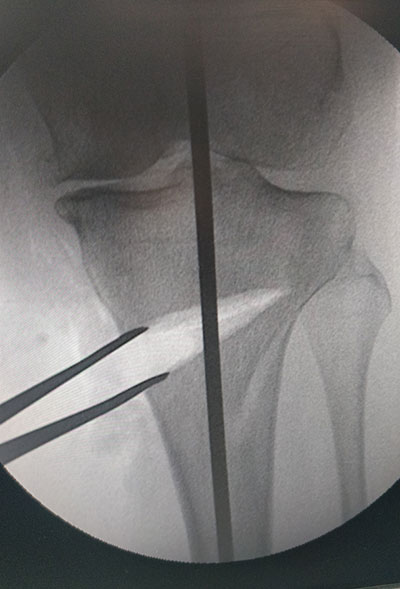

STEPS OF HTO